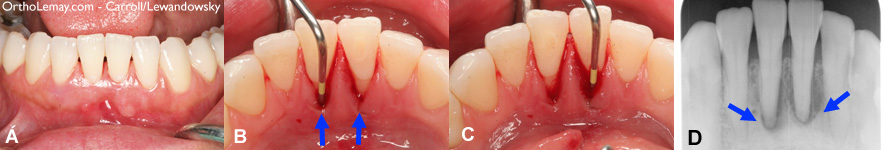

(A) Apparence normale des dents et tissus vue de face. (B et C) La face interne des dents montre une récession gingivale importante, du saignement et une sonde dentaire peut être insérée très profondément indiquant une perte osseuse. (D) une radiographie confirme la perte d’os et le dommage autour des racines des dents.